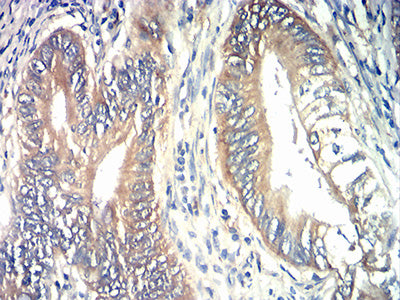

分类: 科研抗体货号: 31838别名: HL-2; HBXBP; ASGPR2; ASGP-R2; CLEC4H2应用: IHC,FCM反应种属: Human

分类: 科研抗体货号: 31855别名: WDM; TIA-1应用: IHC,IF,FCM反应种属: Human